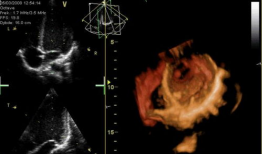

心脏跳动的视频,揭秘心脏跳动的奥秘

你知道吗?最近在网上流传着一个特别神奇的视频,它记录了心脏跳动的瞬间。这可不是普通的视频,它让我们仿佛能感受到心跳的力量,那种感...